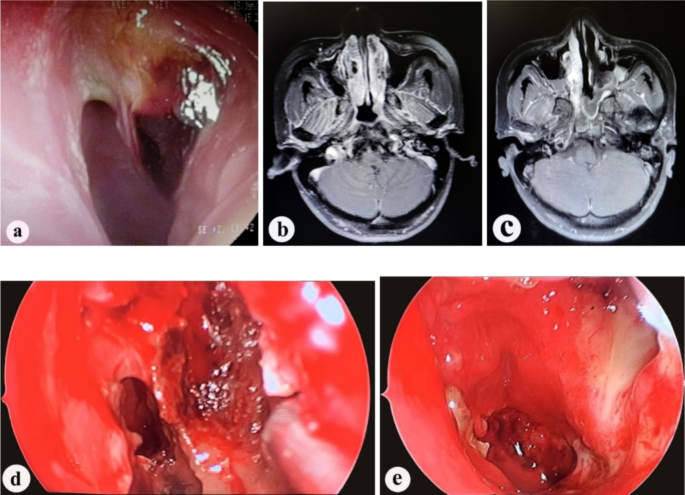

On postoperative day 3, an MRI scan with contrast enhancement of the nasopharynx and skull base is performed to assess the blood supply to the mucosal flap. The blood supply is re-evaluated during the removal of nasal packing under endoscopy. A final assessment of flap viability (survival or necrosis) is conducted at 1 month postoperatively through nasal endoscopic examination。Diagnosis criteria for postoperative flap necrosis: (1) Enhanced MRI suggests poor flap blood supply; (2) Flap color turns pale, dark purple, or black during endoscopic examination; (3) Confirmed absence of normal blood flow by cutting open part of the flap under endoscopy (Fig. 1). This study was approved by the institutional ethics committee of Fujian Cancer Hospital and informed consent was obtained from all patients or their designated proxies. All research was performed in accordance with relevant guidelines/regulations.

(a) Preoperative nasopharyngeal endoscopy shows a mass in the left nasopharynx; ( b) Preoperative enhanced MRI shows enhancement of the mass in the left nasopharynx; (c) Enhanced MRI on the third day post-operation shows good blood supply to the nasal septal mucosal flap. Iodoform gauze packing is visible on the surface of the mucosal flap; ( d) On the fifth day post-operation, after removing the packing, nasal endoscopy shows good blood supply to the nasal septal mucosal flap; (e) One month post-operation, nasal endoscopy shows good blood supply to the nasal septal mucosal flap, which is closely attached to the nasopharynx.